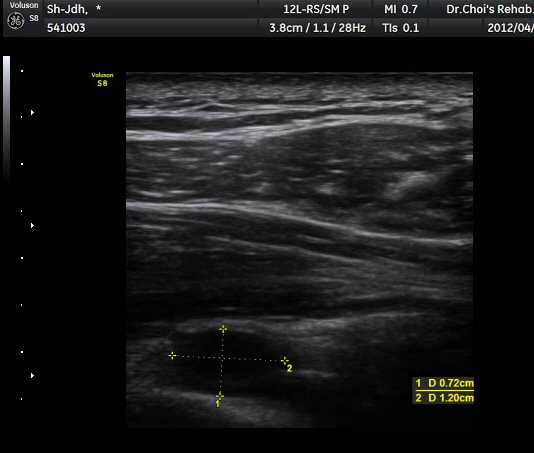

¾î±ú µÚ °üÀý¼ø °Ë»ç¿¡¼­ °üÀý¼ø Ç¥Ãþ¿¡ Àú¿¡ÄÚ ¼ö¾×Àú·ù°¡ °üÂûµÊ(»çÁø 4).

ŽÃËÀÚ¸¦ Á» ´õ µÚ·Î À̵¿ÇÏÀÚ °üÀý¼ø ³»Ãø °¡½Ã°üÀý¿À¸ñÆÐÀÓ(spinoglenoid notch)¿¡

¿øÇü¸ð¾çÀÇ Àú¿¡ÄÚ ³¶Á¾ÀÌ °üÂûµÊ(»çÁø 5, 6).